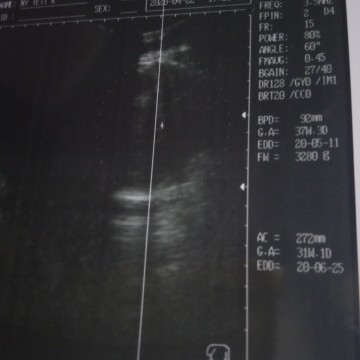

hasil usg

Ada yg ngerti g bunda2?? Ksh tau dong